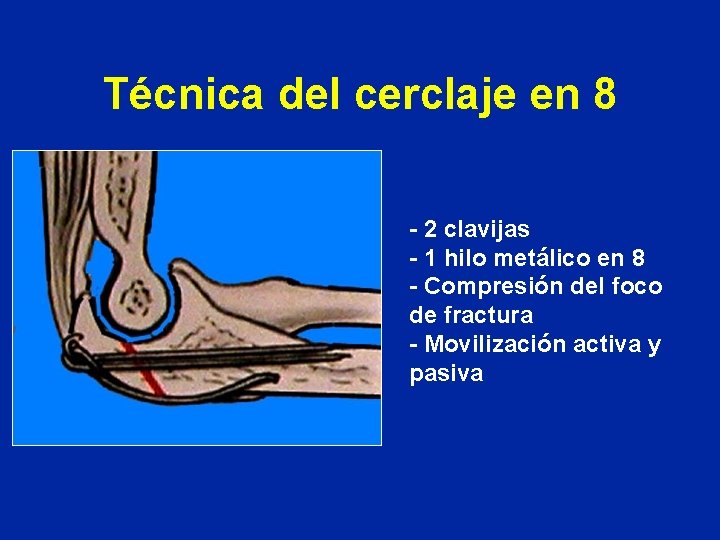

Técnica del cerclaje en 8 - 2 clavijas - 1 hilo metálico en 8 - Compresión del foco de fractura - Movilización activa y pasiva

Técnica del cerclaje en 8 - 2 clavijas - 1 hilo metálico en 8 - Compresión del foco de fractura - Movilización activa y pasiva